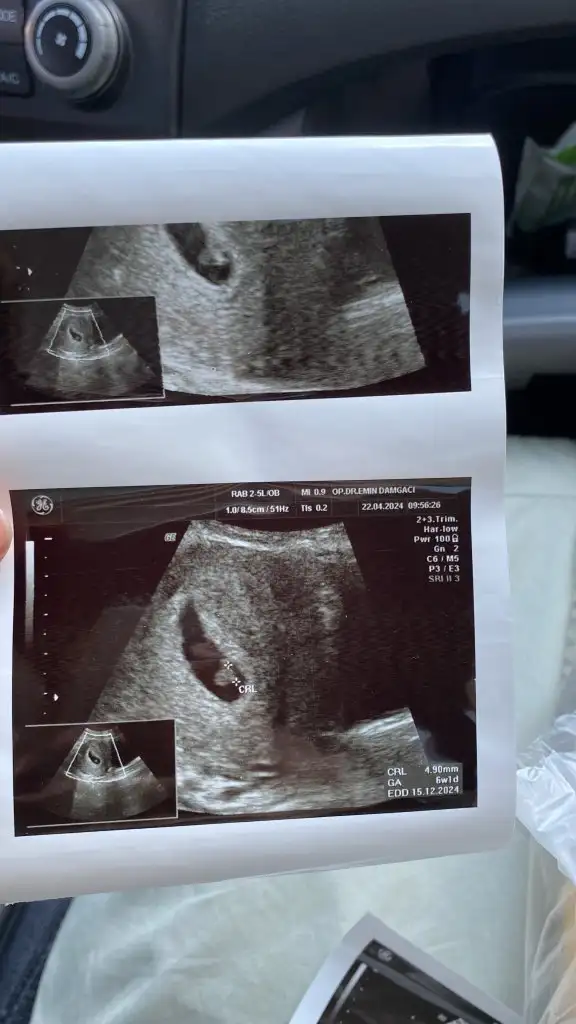

Merhaba benim içinde tahminde bulunabilir misiniz acaba 😊 6+1 karından ultrason

0F282A06-815C-4BCD-84C8-1B3DAE081C87.jpeg